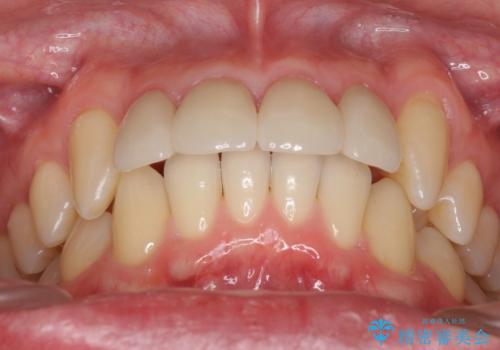

前歯のすき間 セラミックで綺麗に 最短で治療

- 前歯のすき間を気にして来院。

矯正治療か、セラミックで最短で治すかの選択肢を提示し、セラミックで治すことにしました。

利点は、早く終わる上に、保定の必要がないため負担が少ないことが挙げられます。

長年コンプレックスだったすき間が閉じたとのことで、喜んでいただきました。